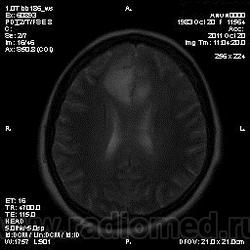

Эта же пациентка... Июль 2011 года....

В анамнезе есть зацепки на энцефалит?Мне ни разу не встречался, поэтому умничать не буду.

мне кажется больше похоже на диффузную глиальную опухоль. Для герпетического нехарактерна локализация и характер контрастирования. Хотя конечно нет правил без исключений..

Евгений Второй, а медиобазальные отделы височных долей - по-моему излюбленная локализация герпетических энцефалитов... Да мне кажется, что серое и белое вещество в равной степени вовлечено в процесс...

а медиобазальные отделы височных долей - по-моему излюбленная локализация герпетических энцефалитов..

Абсолютно согласен, просто у меня не все картинки раньше загрузились и показалось, что все изменения в лобных долях и базальных ядрах. Снимаю свои возражения.